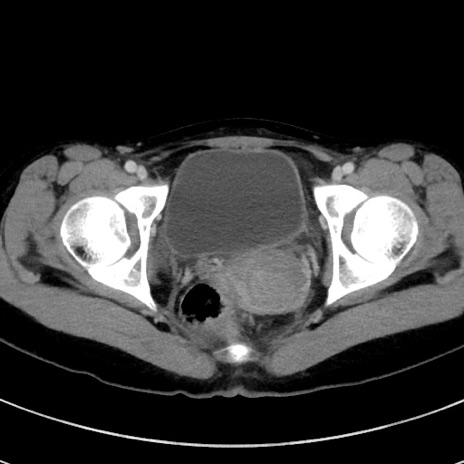

冠状断像

【症例】20歳代女性

【主訴】嘔吐、下腹部痛

【現病歴】昨日夕食後に嘔吐し下腹部痛が出現。本日になっても嘔吐持続し改善しないため来院。

【身体所見】意識清明、BT 37.2℃、BP 108/67mmHg、腹部:平坦、やや硬、下腹部正中から右にかけて圧痛あり、反跳痛軽度あり、tapping pain(+)。

【データ】WBC 13600、CRP 14.94